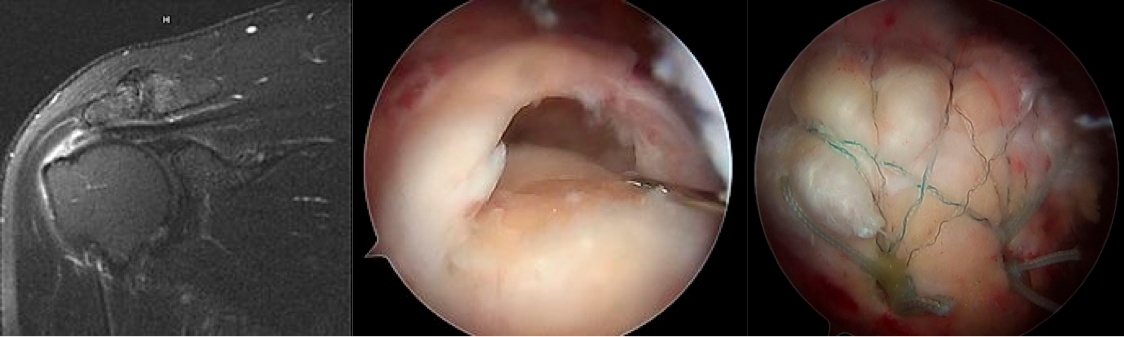

full thickness tear

The coronal MRI far left, initial arthroscopic image middle, and final arthroscopic repair on far right of a full thickness rotator cuff tear.